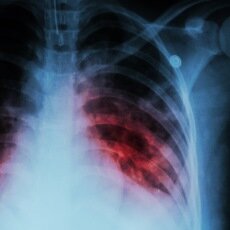

Había un desarrollo masivo de fábricas, que producían gran polución ambiental, donde existía una gran explotación de los obreros, a los que les pagaban salarios paupérrimos. Por estas condiciones laborales los obreros y sus familias vivían en condiciones muy desfavorables, lo que favorecía que fueran víctimas de las enfermedades infecciosas como la Malaria, la Tuberculosis, esta última llegaba a producir 4 000 muertes anuales por cada millón de habitantes.

la Tuberculosis y la Fiebre Tifoidea, casos de los ejemplos señalado anteriormente, tenían ya baja morbilidad y mortalidad, a pesar de que no se habían descubierto todavía los antibióticos y quimioterápicos.